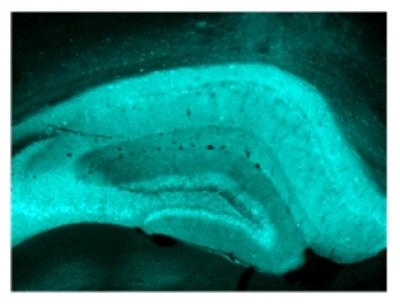

Therefore, how an antidepressant works on the biochemistry and behavior in a mouse in which the CREB protein is deleted only in the hippocampus versus a wild type mouse in which CREM is overexpressed let the researchers tease out the relative influence of CREB and CREM on the pharmacology of an antidepressant. They saw the same results in each type of mouse line – increased nerve-cell generation in the hippocampus and a quicker response to the antidepressant. Their findings appear in the Journal of Neuroscience .

The accelerated time to approach the treat in mice on the medication was accompanied by an increase in new nerve growth in the hippocampus.